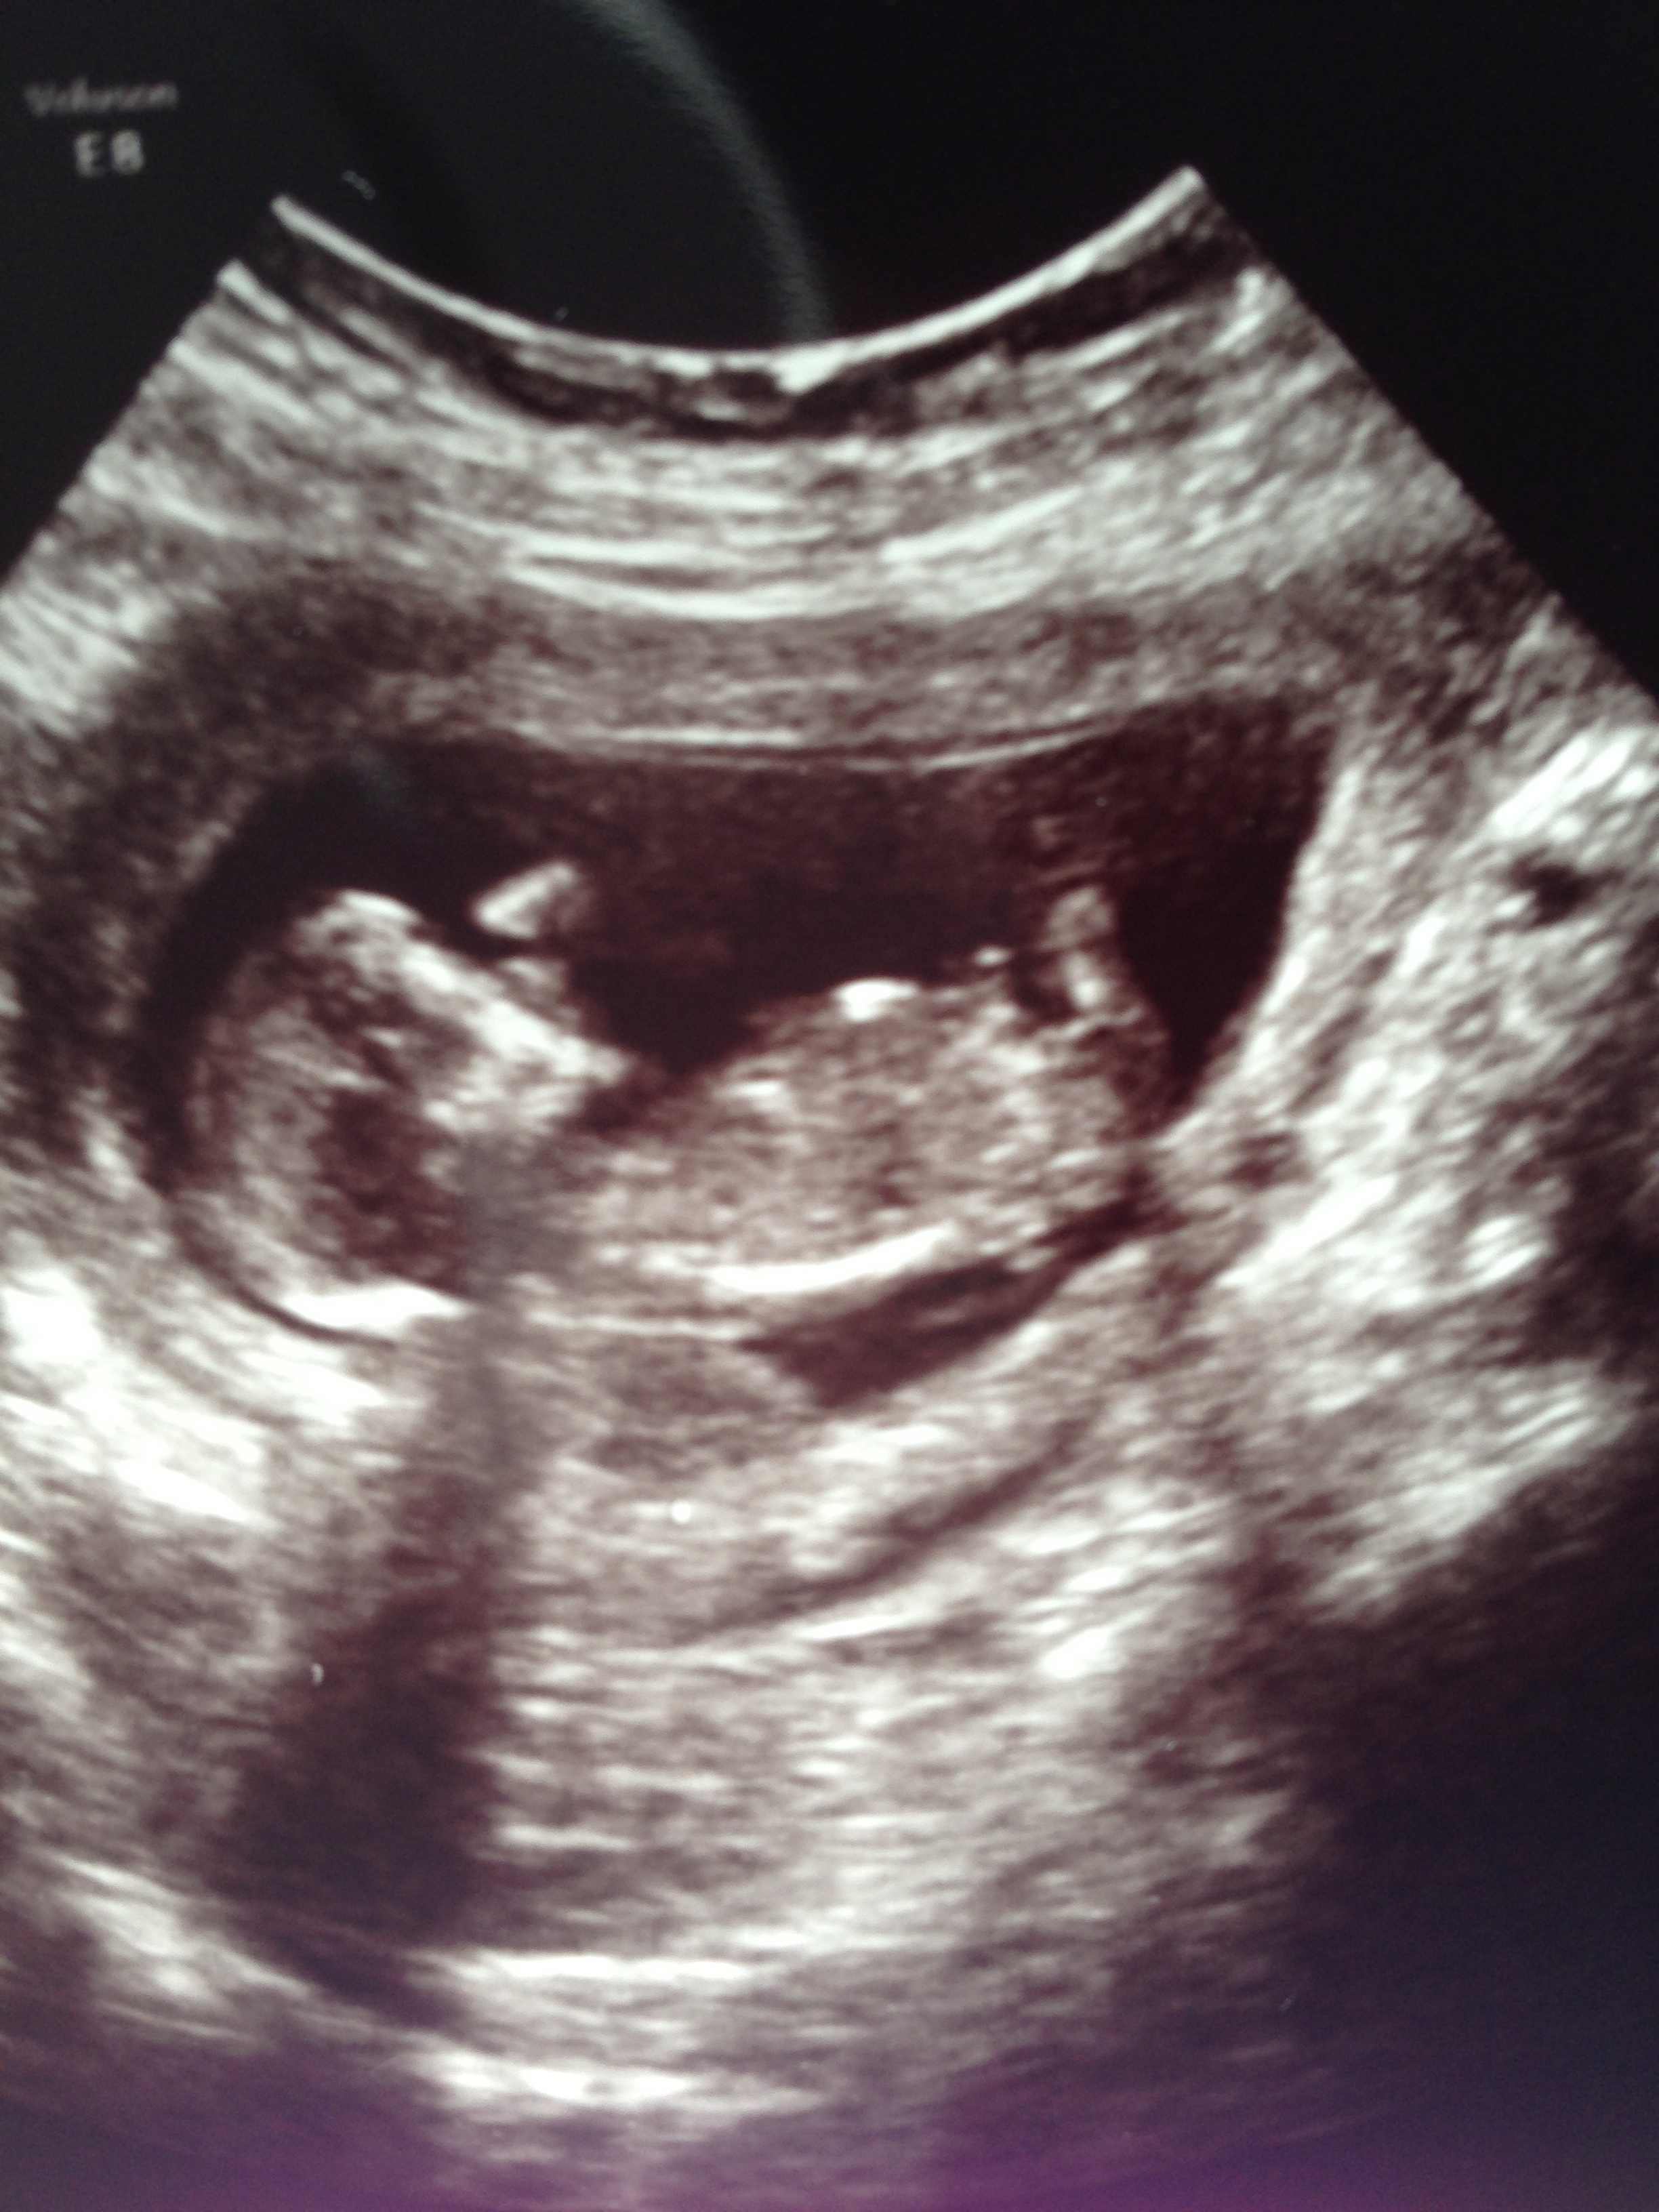

I would say blue based on the last pic but I don't think it's a clear nub shot

Boy guess by last pic. Absolutely not sure, would not be suprised if it turn out to be a girl.

id say blue based on the last pic and skull x

I don't think I see a nub in any picture. I am 50-50. Cute baby though :)

Wow so many boy guesses :)interesting as we had a scan at 13 weeks and our tech had a good look and said she thinks we are having another girl! I can't wait to find out :) that last pic had also thrown me off too although no one on in gender would guess as they as they also said no nub in the pics. So who knows lol love all the guesses though :)